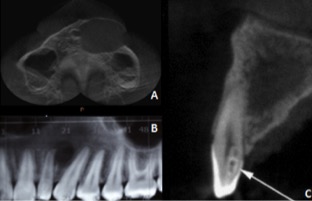

Dens in dente is a dental development malformation that involves more commonly the upper lateral incisors. Infection of the canal of these teeth can cause the formation of chronic periapical lesions. The present study aimed to describe an integrated approach between the endodontic therapy and surgical intervention in an upper lateral incisor with dens in dente type II. A female patient, 14 years old, looked for dental care complaining of left palatal and paranasal bulging. Clinical, radiological and histopathological findings suggested periradicular cyst. First, marsupialization was performed to reduce the size of the lesion and to favor its enucleation, with less risk of injuring the tooth and vital structures. After diagnosis of pulp necrosis and in attempt to reduce the infection via canal, we used the reciprocating instrumentation associated with irrigation with sodium hypochlorite, intracanal medication based on calcium hydroxide and filled with a thermoplastic filling. After a year of marsupialization, fistulectomy and complete enucleation of the lesion were performed. Proservation was performed 1, 3, 6 and 12 months following marsupialization. Six months after enucleation, we observed the periradicular repair and remission of symptoms. The extensive apical lesion associated with dens in dente type II can be treated with a combination of surgical and endodontic therapy.